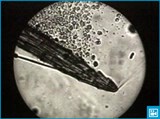

Нейтрофилы — самая большая группа белых кровяных телец, они составляют 50-75% всех лейкоцитов. Свое название они получили за способность их зернистости окрашиваться нейтральными красками. В зависимости от формы ядра нейтрофилы делятся на юные, палочкоядерные и сегментоядерные.

В лейкоформуле юные нейтрофилы составляют не более 1 %, палочкоядерные — 1-5 %, сегментоядерные — 45-70 %. При ряде заболеваний содержание молодых нейтрофилов увеличивается. В крови циркулирует не более 1 % имеющихся в организме нейтрофилов. Основная их часть сосредоточена в тканях. Наряду с этим в костном мозге имеется резерв, превосходящий число циркулирующих нейтрофилов в 50 раз. Выброс их в кровь происходит по первому требованию организма.